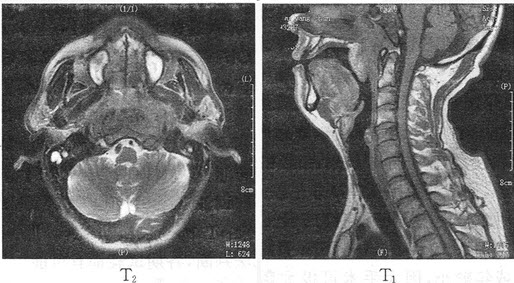

89������ѡ����

�����У�76�ꡣ������ʹ������Ѫ��3���£�MRͼ�����£����п��ܵ�����ǣ���

A.ǰ���ٰ�

B.������

C.����Ϣ��

D.���װ�

E.�����ٰ�